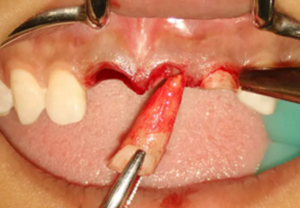

圖7 不翻瓣微創(chuàng)拔牙

(2)即刻種植、即刻臨時修復(fù)。術(shù)中不翻瓣微創(chuàng)拔除牙根,牙槽 窩骨壁完整。在多級導(dǎo)板輔助下完成種植窩洞制備,植入Bego柱形種植 體,型號分別為:上頜右側(cè)中切牙位點(diǎn)4.1mm×15mm、上頜左側(cè)中切牙 位點(diǎn)?3.75mm×15mm、上頜左側(cè)側(cè)切牙位點(diǎn)3.25mm×15mm,扭矩均為 35N·cm。種植體與唇側(cè)骨壁間隙約2mm,植入Bio-Oss®Collagen骨膠 原。戴入橋用鈦臨時基臺,臨時冠就位順利,自凝樹脂口內(nèi)粘接后適當(dāng)修整 外形,充分磨光,調(diào) 至正中 、前伸 和側(cè)方 與對頜牙均無接觸。術(shù)后 根尖片顯示種植體位置、方向良好。